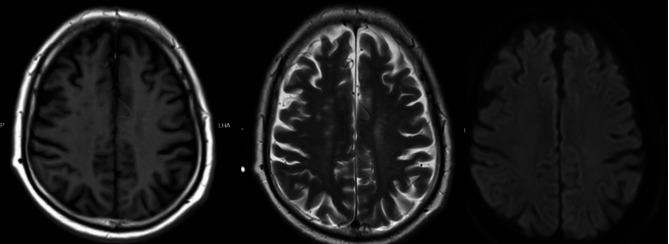

病例报告:以直立性低血压为首发表现的进行性脑脊髓炎伴僵硬和肌阵挛(PERM)伴多种自身免疫抗体。

Case report: orthostatic hypotension as the first presentation of progressive encephalomyelitis with rigidity and myoclonus (PERM) with multiple autoimmune antibodies.

This case presents a 71-year-old man who was ultimately diagnosed with progressive encephalomyelitis with rigidity and myoclonus (PERM). His initial symptom was orthostatic hypotension, and we detected multiple antibodies such as GlyR antibody, GAD antibody, GM1-IgG and GQ1b-IgG in his serum. The patient showed partial response to glucocorticoid and immunoglobulin therapies, but as the disease recurred and progressed, plasma exchange, rituximab, and cyclophosphamide immunosuppressive therapy was administered, the prognosis remained poor. During follow-up after treatment, the patient developed pulmonary embolism and cardiac arrest, and died.

本病例报告了一位 71 岁男性,最终被诊断为进行性脑脊髓炎伴僵硬和肌阵挛(PERM)。他的初始症状是直立性低血压,我们在他的血清中检测到多种抗体,如 GlyR 抗体、GAD 抗体、GM1-IgG 和 GQ1b-IgG。该患者对糖皮质激素和免疫球蛋白治疗有部分反应,但随着疾病复发和进展,给予了血浆置换、利妥昔单抗和环磷酰胺免疫抑制治疗,但预后仍较差。治疗后随访期间,患者发生肺栓塞和心脏骤停,最终死亡。